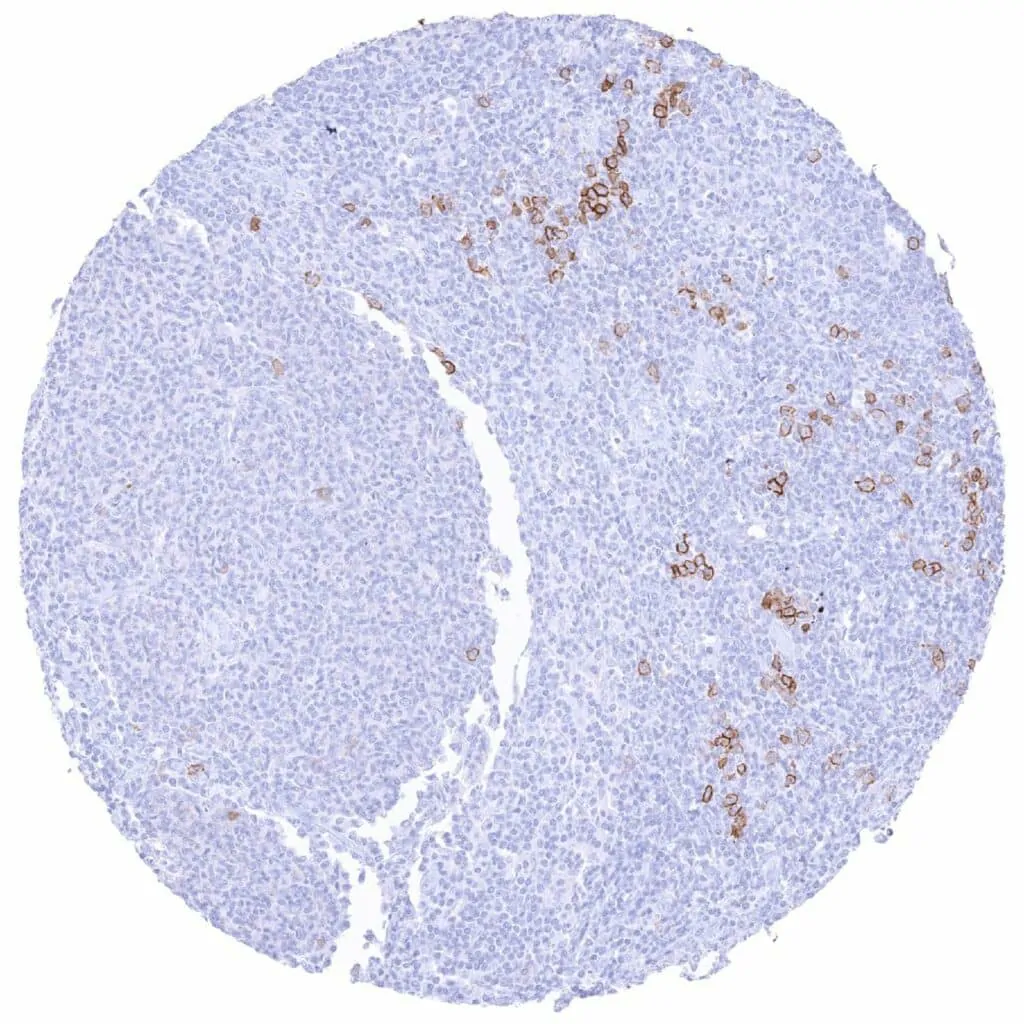

Lymph node – CD38 negative Hodgkin’s lymphoma. A fraction of associated inflammatory cells are CD38 positive